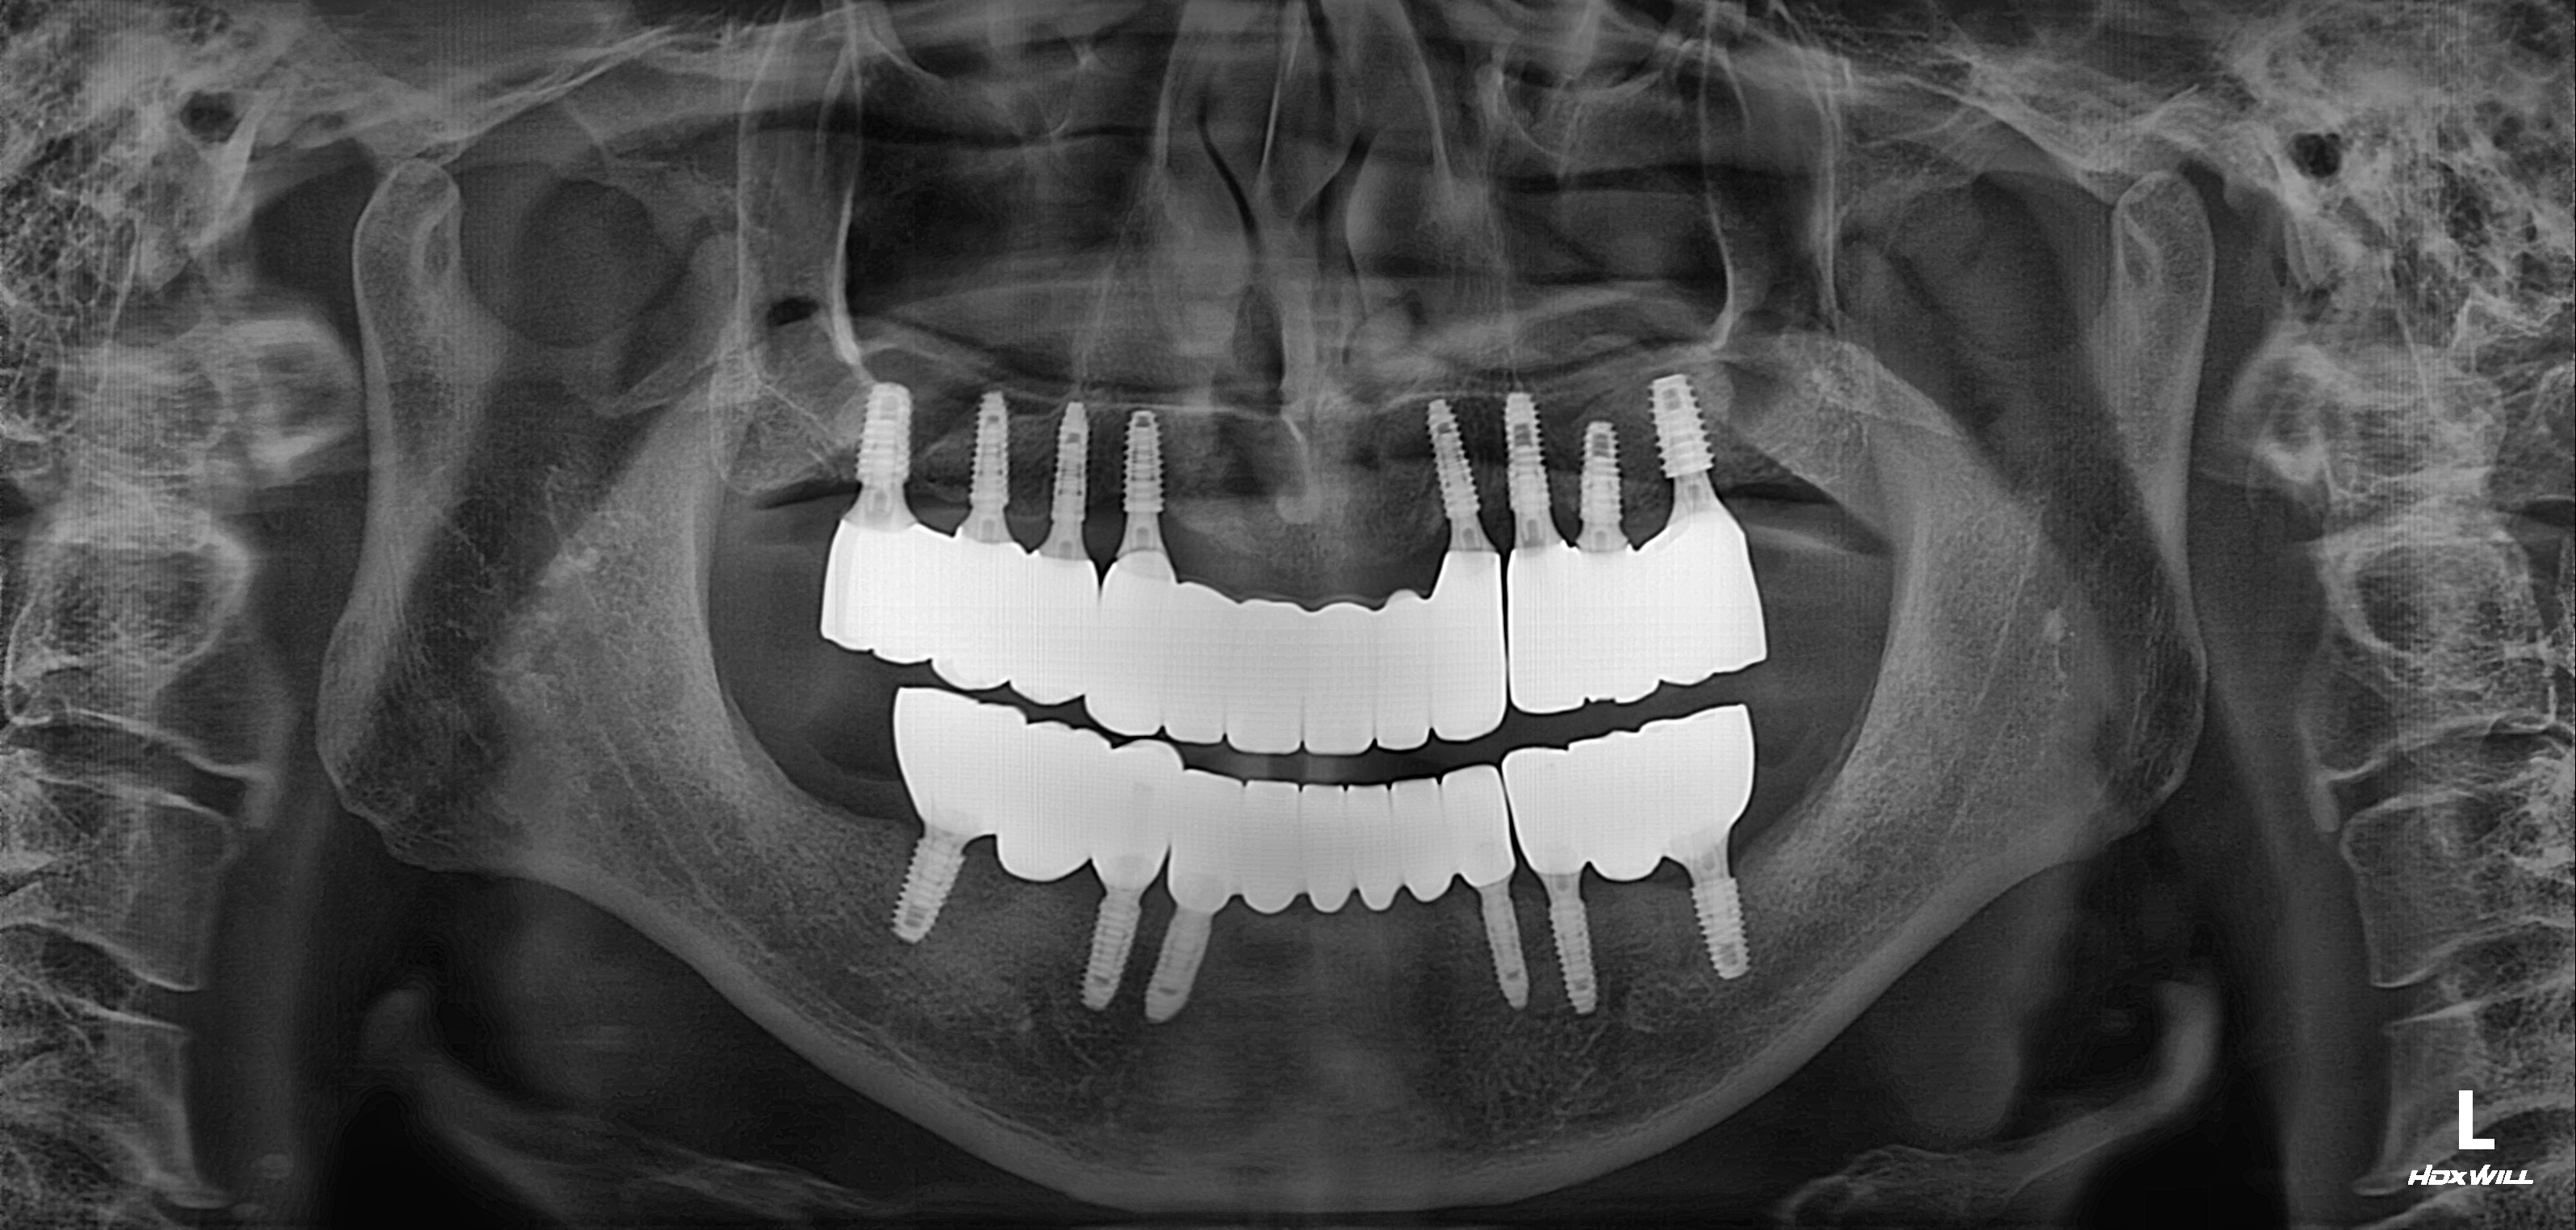

수술 전

수술 후

상악 임플란트 식립사례

전후사진